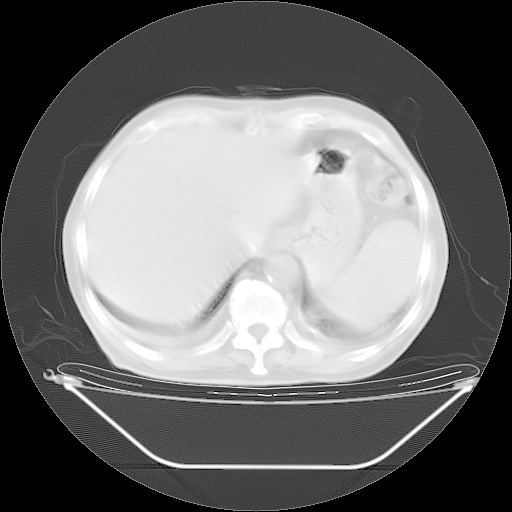

胸腹部CT,诊断意见:左上肺叶钙化灶、左侧胸膜局限性增厚并钙化、胆囊炎。描述部分肺组织呈磨玻璃样改变。